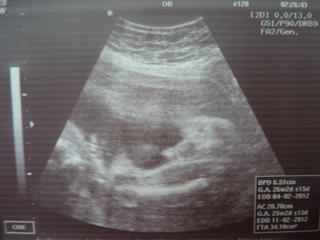

Ve čtvrtek jdeme na 3D ultrazvuk, tak jsme moc zvědaví 🙂

ahojte, my máme termín 24.2.2012 tak sa nevieme dočkať 🙂 my sme boli túto sobotu na 4D ultrazvuku, a fakt parádny zážitok odporúčam 🙂